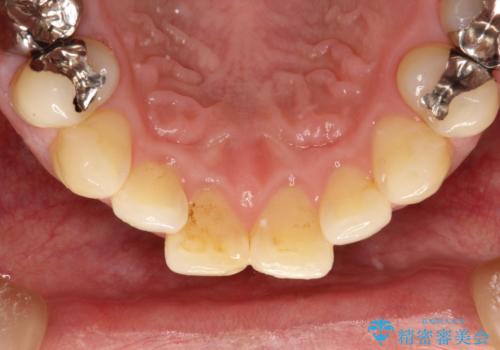

- 治療計画

- 歯科でのクリーニングがかなり久しぶりで口臭も気になるとのことで来院されました。PMTCの60分コースで、染め出し・ブラッシング指導・クリーニングを行いました。

口臭は、様々なことからの原因がありますが、お口の中の細菌が繁殖することにより発生するともいわれています。多くの場合は正しい歯磨きを習慣づけることで、減少されます。毎日のご自身でのケアと、定期的に歯科医院にてPMTCを受けることにより、息をさわやかにすることができます。

適切な歯磨き方法を習得するには、染め出しを行い、磨き残しを把握していくことがポイントです。

磨けているよう、磨いているつもりでも、汚れが残ってしまうと、毎日の歯磨き時間が無駄になってしまうこともあります。効率的に歯磨きを行い、磨き残しを減らせるように、歯科衛生士による専門的な指導を行います。